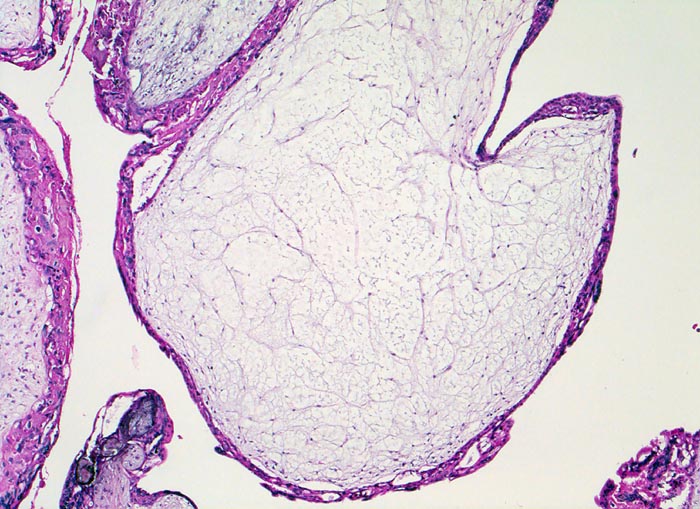

Blasenmole

Die Plazentarzotten sind aufgetrieben, das Stroma ist ödematös und enthält keine Gefässe. Das Trophoblastepithel ist verdickt (normal zweilagig).

beta HCG Level von 150'000 mIU/mL. Uterus zu gross für das Gestationsalter von 10 Wochen. Arterielle Hypertonie.

Histologie

50